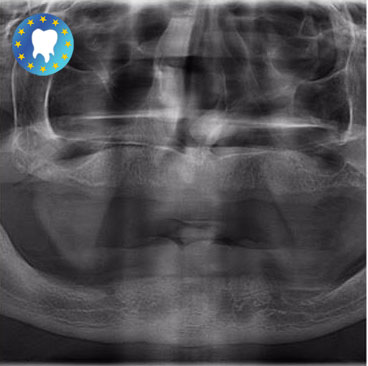

Ce patient est parti à Budapest en Hongrie pour effectuer ses soins dentaires.

Ses soins dentaires ont lieu en deux étapes:

-Dans un premier temps la pose des implants dentaires.

-Puis la poses des couronnes dentaires (12 en haut et 12 en bas).